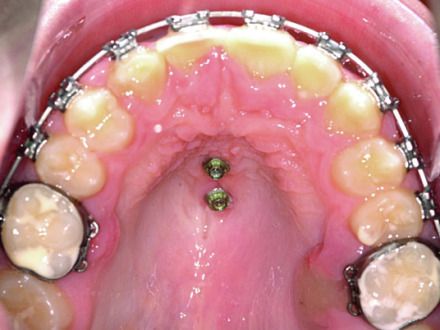

Gaumenimplantat

Im vorliegenden Fall hilft ein Gaumenimplantat mit einer entsprechenden Apparatur die Mahlzähne nach hinten (distal) zu bewegen, um eine korrekte Verzahnung einzustellen oder einen Engstand ohne Extraktion und ohne abnehmbare Geräte (z.B. Headgear) aufzulösen.

Auch die Gaumenapparatur „Top Jet“ mit zwei Minischrauben im Gaumen ermöglicht eine Distalisierung der Mahlzähne, ohne dass eine Mitarbeit der Patient:innen notwendig wäre (ersetzt den Headgear). Indem der Top Jet innen befestigt wird und die Brackets auf den Frontzähnen am Beginn der Behandlung noch nicht notwendig sind, erfolgt der erste Teil der Behandlung unsichtbar und damit ohne ästhetische Beeinträchtigung.